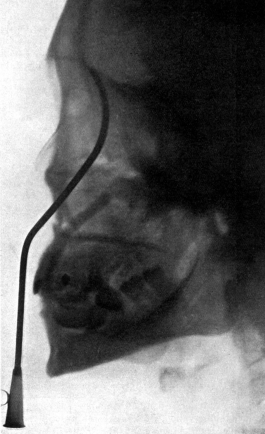

| 334. | Radiograph to show the Value of the Röntgen Rays | 639 |

| 335. | Radiograph showing Canula in the Frontal Sinus | 639 |